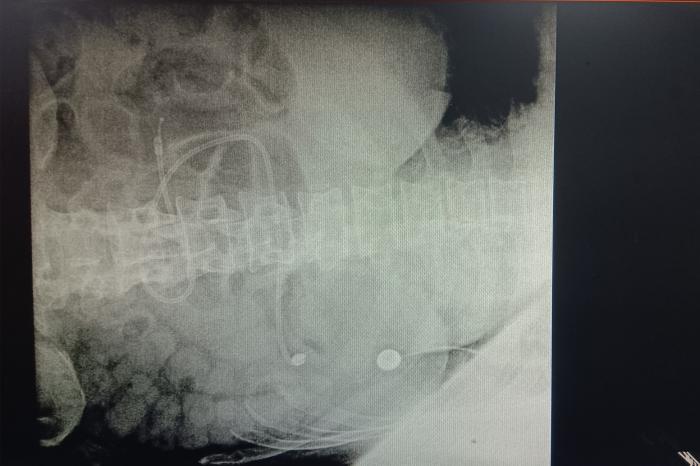

三腔喂养管的置入有盲插法、B超引导下置入法和胃镜下置入法等多种途径,可以满足不同患者的临床需求。其中盲插法具有费用低,创伤小,操时间短等优势,但操作难度较高,最能考验操作者的专业技术。操作当天,责任护士唐海娟为欧先生量置入距离,并记下该刻度,润滑前端,从鼻腔插入,进入到55cm,双人核对在胃里后,换成执笔手法继续置入,置入最终深度,最后拍腹部平片,确认到达十二指肠,置管成功。这是神经内一科的第一例三腔喂养管置入术,也是湘南学院附属医院首例床旁盲插三腔喂养管置入术。